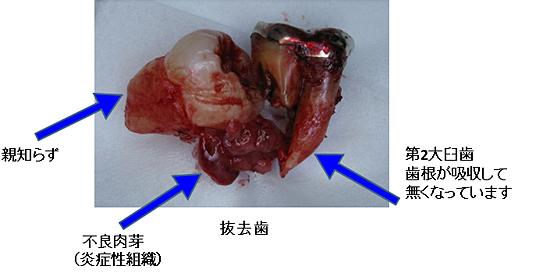

抜歯後の不良肉芽組織の除去はとても大切小嶋デンタルクリニック。

抜歯後の不良肉芽組織の除去はとても大切小嶋デンタルクリニック。